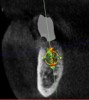

(9.) Virtual plan showing that the extraction of tooth No. 20 followed by robot-assisted immediate implant placement at the sites of teeth Nos. 19 and 21 was a viable option.

Figure 9

(10.) Crown location at site No. 19 optimized on the virtual plan.

Figure 10

(11.) Implant position at site No. 21 optimized on the virtual plan.

Figure 11